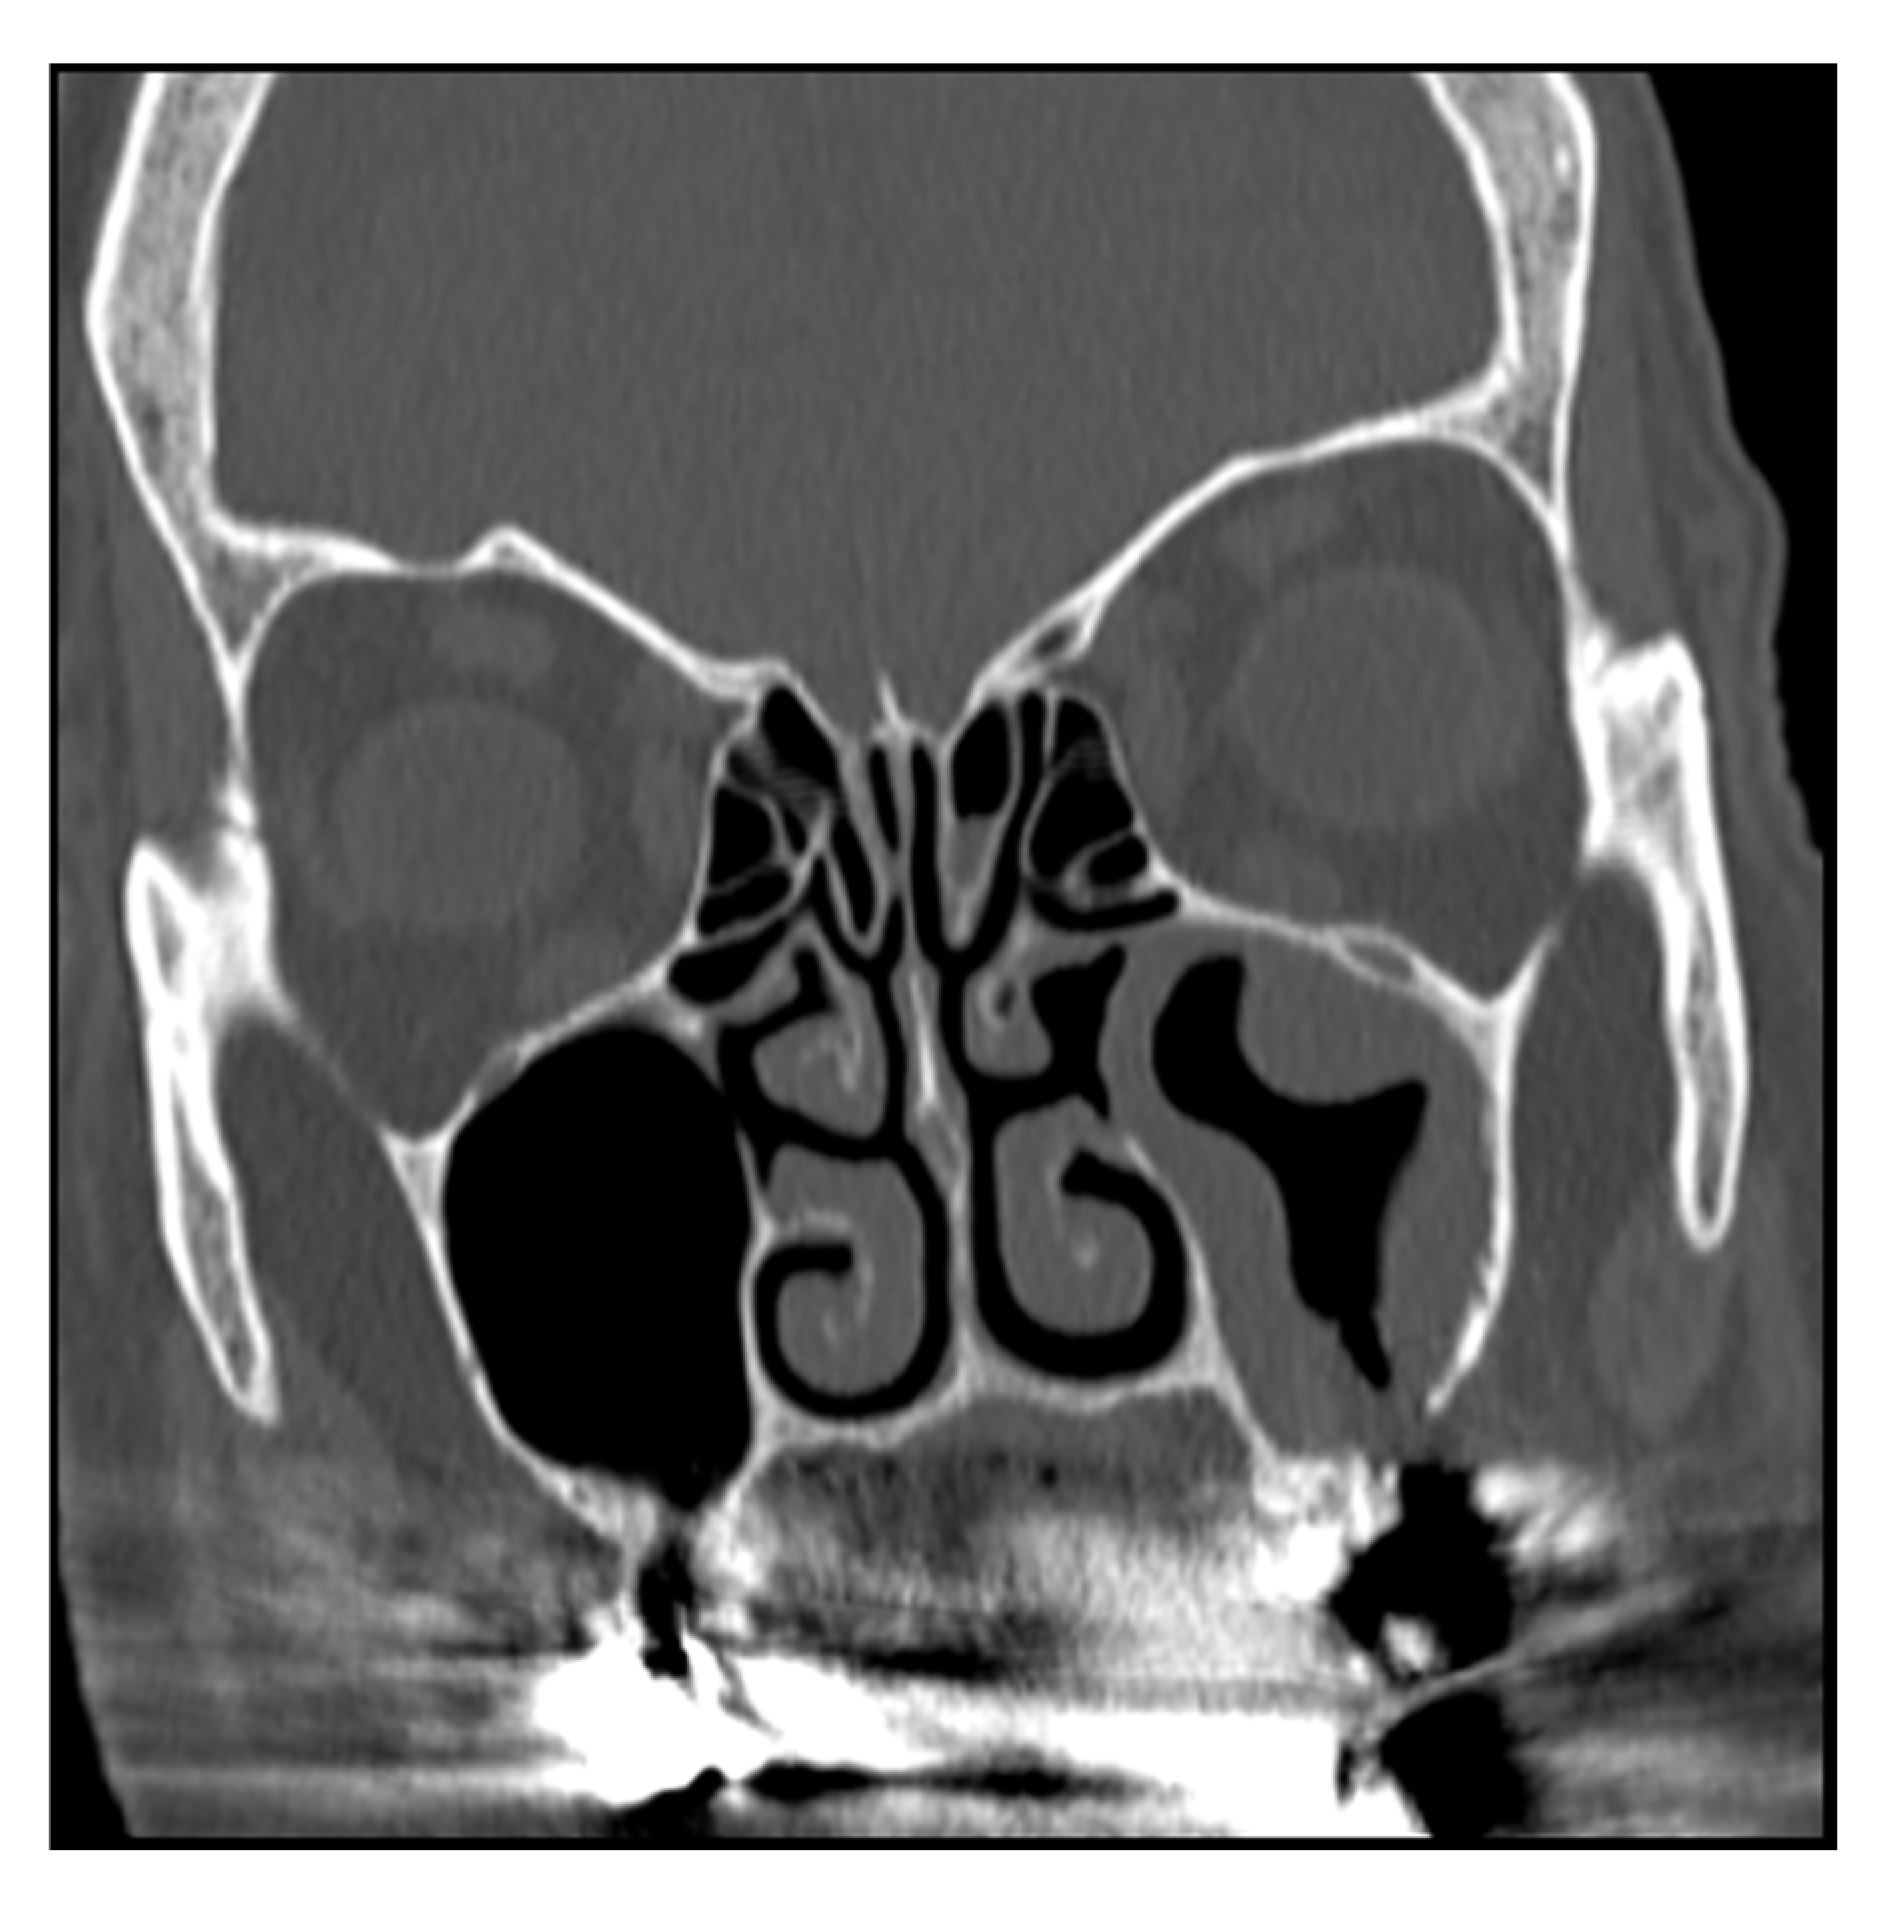

• A patient suffering from sinusitis due to a complication of implantological treatment for at least 4 months, with OAF, without obstruction of ostiomeatal complex and without foreign body can be identified as: TcEaB0O0F1 [Figure 1] [Figure 2]

Figure 1. Slice TC 1 of patient with TcEaB0O0F1.